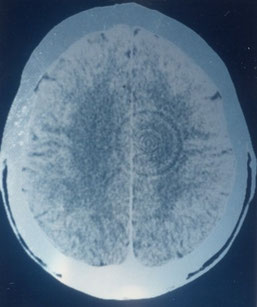

Hamer behauptet, im Hirn-CT (cCT) von Krebspatienten Veränderungen entdecken zu können, die einer Schießscheibe ähneln, also so gen. konzentrische Kreise.

Zur Art der "Hamer-Herde" stellen sich sofort zwei Fragen, die von Hamer nirgends beantwortet werden. Er beharrt zwar ständig darauf, dass diese Erscheinungen keine Artefakte (Darstellungsfehler) der Computertomographie seien, ist aber nicht in der Lage, dafür einen stichhaltigen Beweis zu liefern.

Zusammenfassung: Wie dem auch sei, Hamer schweigt sich über das morphologische Korrelat seiner Herde aus. Aber eines wird klar: wenn sie immer als konzentrische Kreise auf einem CT abgebildet werden, müssen sie von sehr gleichmäßiger innerer und äußerer Struktur sein. Aus technischen bzw. stochastischen Gründen scheiden der Zylinder, der Kegel und die Scheibe und alle ihre Abwandlungen als morphologisches Korrelat aus. Bleibt also nur die Kugel. Die müsste jedoch auch in weiteren Bildern erkennbar sein, wobei der Schnitt von Bild zu Bild an Größe entweder zu- oder abnimmt. Es ist jedoch sehr unwahrscheinlich, dass im Rahmen eines krankhaften Geschehens immer ein exakt kugelrundes Gebilde an verschiedenen Orten des Gehirns auftritt. Weder in der Anatomie noch in der Pathologie sind größere, d.h. im CT erkennbare exakt kugelrunde Strukturen bekannt. Auch wurden bislang aus den Reihen Hamers nie Bildfolgen einer Computertomographie mit so gen. Hamer-Herden auf mehreren Bildern, die o.a. Kriterien entsprechen, veröffentlicht.

Warum sind „Hamer-Herde“ nur im CT nachweisbar? Von Kritikern und Radiologen werden die „Hamer-Herde“ von jeher als Artefakt bezeichnet (siehe: Stellungnahmen zum Thema). Diese Ringartefakte waren bei CT-Geräten der 3. Generation (ab 1974), die Hamer bei seiner "Entdeckung" Anfang der 80er Jahre verwendet haben dürfte, bekanntermaßen keine Seltenheit, treten aber bei moderneren CTs so gut wie nicht mehr auf.

Allein diese beiden Kriterien genügen, um nachzuweisen, ob es sich bei den "Hamer-Herden" um Artefakte handelt oder nicht. Wenn eine im cCT entdeckte Ringstruktur an gleicher Stelle auch im NMR sichtbar ist, kann es sich logischerweise nicht um ein Artefakt des CT handeln, denn die Technik des NMR unterscheidet sich grundlegend von der des CT. Im CT wird mit Röntgenstrahlen gearbeitet, im NMR mit magnetischen Impulsen. Außerdem wäre ein Hamer-Herd zweifelsfrei kein Artefakt, wenn er bei einem erneuten cCT in anderer Position des Patienten oder anderer Schnittbildführung wieder an gleicher Stelle des Patienten erscheint. Merkwürdigerweise hat Hamer diese Möglichkeit des Nachweises für die Richtigkeit seiner Theorie – zumindest offiziell - nie genutzt, und bis heute sprechen alle Anhänger der "GNM" nur immer vom CT, nie aber vom NMR. Das mutet seltsam an, da doch die Kernspintomographie seit Jahren etabliert und im Gegensatz zum CT strahlungsfrei ist. Natürlich kann man getrost davon ausgehen, dass Hamer bei allen seinen Bemühungen, die "(G)NM" zu "verifizieren", auch versuchte, seine Herde im NMR zu finden. Hätte er sie gefunden, so wäre dies ein Beweis für die Richtigkeit seiner These und mit an Sicherheit grenzender Wahrscheinlichkeit von ihm sofort veröffentlicht worden, spätestens auf Pilhars Web-Seite. Es ist jedoch kein einziger Fall bekannt, bei dem ein Hamer-Herd aus dem CT auch im NMR nachgewiesen worden wäre. Das Nichtvorhandensein eines solchen Falles ist daher so zu interpretieren, dass die Hamer-Herde im NMR nicht gefunden werden konnten und sie somit als Artefakt des CT mit veralteter Technik zu werten sind. Auch über die Möglichkeit des Nachweises anhand einer Lageänderung oder einer anderen Schnittbildführung im CT gibt es keine einzige Veröffentlichung auf den einschlägigen GNM-Seiten, wobei man auch hier davon ausgehen kann, dass Hamer dies mit Sicherheit versucht hat, aber auch hier scheiterte und die Sache unkommentiert unter den Tisch fallen ließ. Die artifizielle Genese der "Hamer-Herde" wird zudem durch die wenigen Beispiele deutlich, die sich auf GNM-freundlichen Seiten finden. Das eindruckvollste Beispiel ist ausgerechnet auf der Seite von Pilhar zu finden: [6]. (Siehe auch das Bild zu Beginn des Abschnitts). Sieht man sich einmal den so gen. Hamerschen Herd an, der auf dieser Seite abgebildet ist, fällt sofort auf, dass sich dieser über die Trennung der beiden Großhirnhälften erstreckt. Sogar die Ringstruktur wird durch die so gen. Fissura longitudinalis cerebri deutlich durchbrochen, so dass zwei ungleich große Teile eines Kreises entstehen. Das gleiche gilt für mehrere „Hamer-Herde“, die sich auf den Umschlagsseiten von italienischen Büchern des italienischen Vereins ALBA finden, sowie auf weiteren CTs auf dieser Seite: [7]

Dies macht deutlich, dass es sich in diesen Fällen nicht um eine anatomische Struktur, sondern nur um ein Artefakt handeln kann, denn welche Struktur kann ohne Verbindung von einem Organteil in ein anderes wachsen oder entstehen, wobei der Verlauf der Grenzstrukturen weiterhin exakt eingehalten wird?